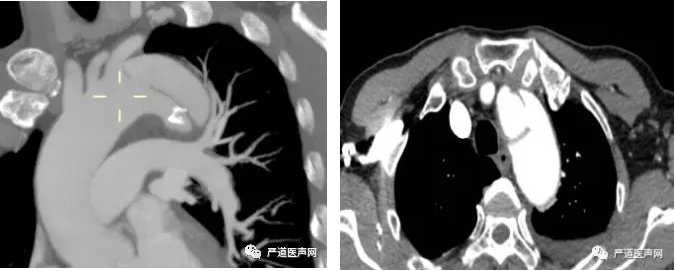

主动脉CTA提示:主动脉夹层(Stanford B型、DeBakey III型),破口位于主动脉弓层面左锁骨下动脉开口以远,病变向前逆撕至LSA开口前缘,向下累及至双侧髂总动脉以远,其中腹腔干、肠系膜上动脉、双侧肾动脉及双侧髂内外动脉均由真腔供血,双侧肾动脉平面以下假腔血栓化改变。

术前主动脉CTA

TEVAR+ IA chimney术前主动脉造影

造影结果示:主动脉弓上分流血管血流通畅,患者为主动脉夹层(Stanford B型、DeBakey III型),破口位于主动脉弓-左锁骨下动脉开口以远处并逆撕至左锁骨下动脉开口前缘。结合术前主动脉CTA诊断结果,决定行胸主动脉腔内隔绝术+头臂干烟囱支架植入术。